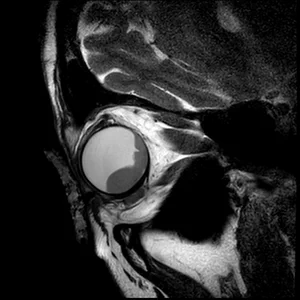

• 3DT1 SPIR Gd

3DT1 SPIR Gd

The isotropic resolution allows for accurate 3D assessment of the lesion dimensions.